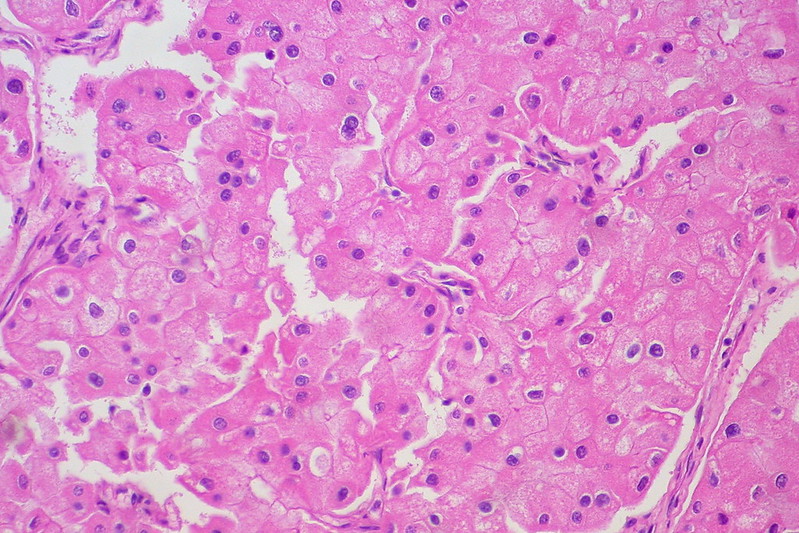

Renal Cell Carcinoma (RCC)

Renal cell carcinoma (RCC) is a malignant cancer cells are located in the lining of kidney tubules, which are incredibly tiny tubes. This condition is known as renal cell carcinoma.

When examined under a microscope, the most common variant of renal cell carcinoma shows clear cytoplasm or a clear cell type.

Loss of the tumor suppressor gene VHL causes an increase in the growth-promoting hormone IGF-1 and the transcription factor HIF, which in turn causes an increase in the growth hormones VEGF and PDGF.